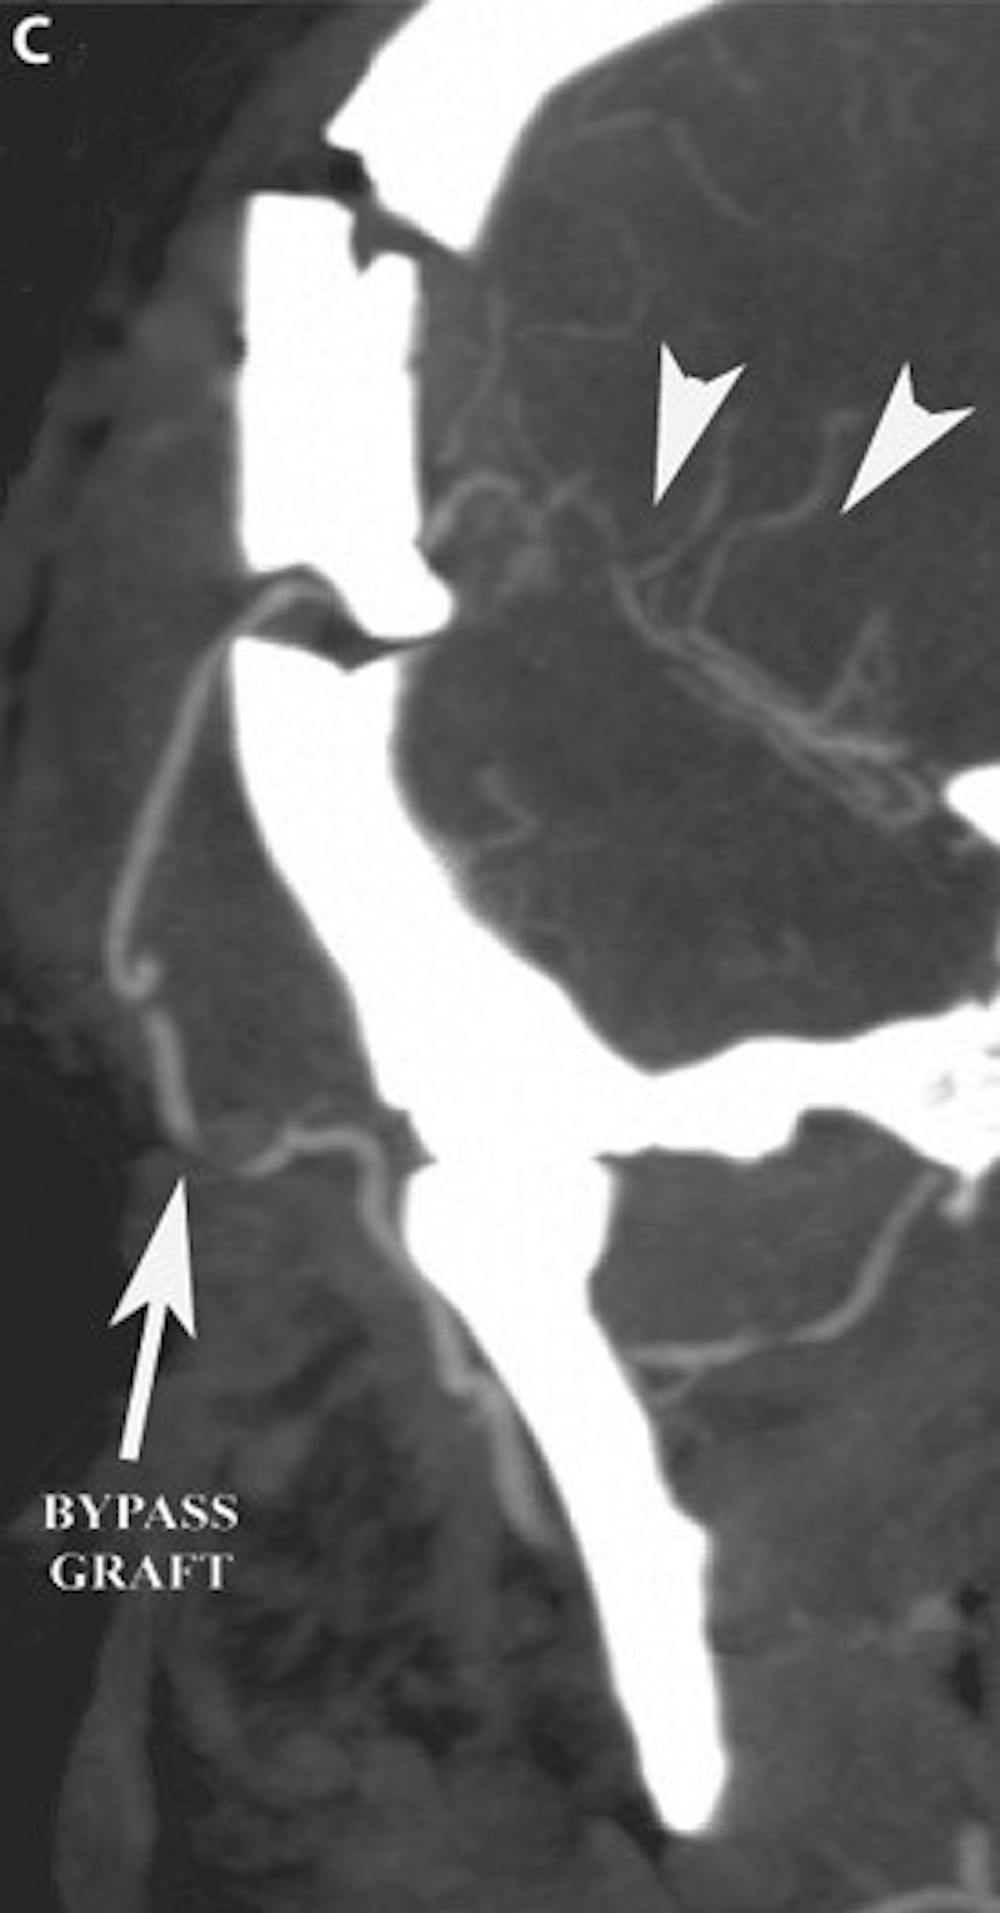

सी) पोस्ट-ऑपरेटिव कोरोनल सीटी एंजियोग्राम पेटेंट बाईपास ग्राफ्ट और पुनरोद्धारित मध्य सेरेब्रल धमनी क्षेत्र (एरोहेड्स) को प्रदर्शित करता है।